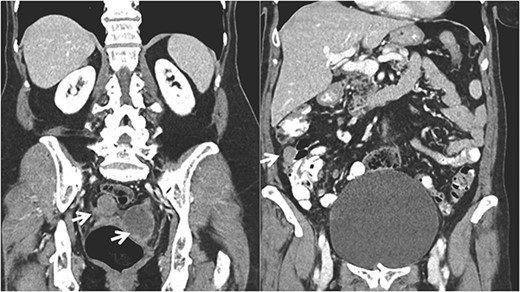

A 68-year-old patient, initially diagnosed with a FIGO stage IIA fallopian tube carcinoma, was under active follow-up in the Gynecologic Oncology Clinic at our institution since 2020. She underwent primary cytoreductive surgery in August 2019 (hysterectomy, bilateral salpingo-oophorectomy, omentectomy, pelvic and para-aortic lymphadenectomy, without any residual macroscopic disease) and completed six cycles of postoperative chemotherapy (carboplatin and paclitaxel) in January 2020. She was free of disease until May 2022 (disease free interval—26 months) when her CA 125 began to rise (52 U/L). CT and MRI scans showed splenic and subcapsular hepatic implants, two metastatic pelvic nodules with 31 and 58 mm next to the sigmoid colon and rectum, and several mesenteric implants in the descendent colon (Figs 1 and 2).

Coronal CT imaging showing the pelvic tumor implants and in the right colon.